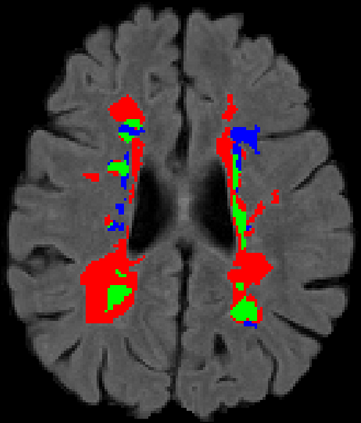

Recently, segmentation methods based on Convolutional Neural Networks (CNNs) showed promising performance in automatic Multiple Sclerosis (MS) lesions segmentation. These techniques have even outperformed human experts in controlled evaluation conditions such as Longitudinal MS Lesion Segmentation Challenge (ISBI Challenge). However state-of-the-art approaches trained to perform well on highly-controlled datasets fail to generalize on clinical data from unseen datasets. Instead of proposing another improvement of the segmentation accuracy, we propose a novel method robust to domain shift and performing well on unseen datasets, called DeepLesionBrain (DLB). This generalization property results from three main contributions. First, DLB is based on a large group of compact 3D CNNs. This spatially distributed strategy ensures a robust prediction despite the risk of generalization failure of some individual networks. Second, DLB includes a new image quality data augmentation to reduce dependency to training data specificity (e.g., acquisition protocol). Finally, to learn a more generalizable representation of MS lesions, we propose a hierarchical specialization learning (HSL). HSL is performed by pre-training a generic network over the whole brain, before using its weights as initialization to locally specialized networks. By this end, DLB learns both generic features extracted at global image level and specific features extracted at local image level. DLB generalization was validated in cross-dataset experiments on MSSEG'16, ISBI challenge, and in-house datasets. During experiments, DLB showed higher segmentation accuracy, better segmentation consistency and greater generalization performance compared to state-of-the-art methods. Therefore, DLB offers a robust framework well-suited for clinical practice.